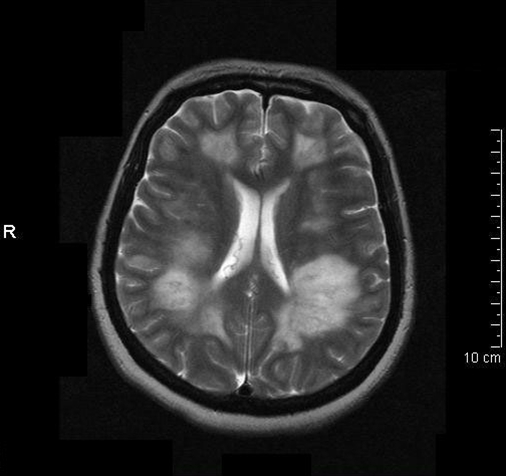

- Typiske fund på MRI:

- Diffuse, dårligt demarkerede, store (>1-2 cm) T2 læsioner, som overvejende involverer den cerebrale hvide substans

- T1 hypointense læsioner i den hvide substans er sjældne

- Grå substans læsioner, enten kortikale eller i thalamus/basalganglier (ca. 50%)

- Gadolinium opladende læsioner er til stede i varierende omfang